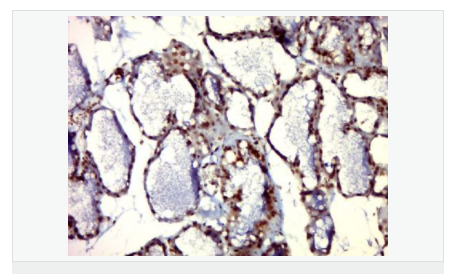

| 產(chǎn)品應(yīng)用 | WB=1:500-2000 ELISA=1:5000-10000 IHC-P=1:100-500 IHC-F=1:100-500 IF=1:100-500 (石蠟切片需做抗原修復(fù)) not yet tested in other applications. optimal dilutions/concentrations should be determined by the end user. |

| 產(chǎn)品介紹 | The protein encoded by this gene belongs to the Ser/Thr protein kinase family, and PIM subfamily. This gene is expressed primarily in B-lymphoid and myeloid cell lines, and is overexpressed in hematopoietic malignancies and in prostate cancer. It plays a role in signal transduction in blood cells, contributing to both cell proliferation and survival, and thus provides a selective advantage in tumorigenesis. Both the human and orthologous mouse genes have been reported to encode two isoforms (with preferential cellular localization) resulting from the use of alternative in-frame translation initiation codons, the upstream non-AUG (CUG) and downstream AUG codons (PMIDs:16186805, 1825810).[provided by RefSeq, Aug 2011]. Function: Proto-oncogene with serine/threonine kinase activity involved in cell survival and cell proliferation and thus providing a selective advantage in tumorigenesis. Exerts its oncogenic activity through: the regulation of MYC transcriptional activity, the regulation of cell cycle progression and by phosphorylation and inhibition of proapoptotic proteins (BAD, MAP3K5, FOXO3). Phosphorylation of MYC leads to an increase of MYC protein stability and thereby an increase of transcriptional activity. The stabilization of MYC exerced by PIM1 might explain partly the strong synergism between these two oncogenes in tumorigenesis. Mediates survival signaling through phosphorylation of BAD, which induces release of the anti-apoptotic protein Bcl-X(L)/BCL2L1. Phosphorylation of MAP3K5, an other proapoptotic protein, by PIM1, significantly decreases MAP3K5 kinase activity and inhibits MAP3K5-mediated phosphorylation of JNK and JNK/p38MAPK subsequently reducing caspase-3 activation and cell apoptosis. Stimulates cell cycle progression at the G1-S and G2-M transitions by phosphorylation of CDC25A and CDC25C. Phosphorylation of CDKN1A, a regulator of cell cycle progression at G1, results in the relocation of CDKN1A to the cytoplasm and enhanced CDKN1A protein stability. Promote cell cycle progression and tumorigenesis by down-regulating expression of a regulator of cell cycle progression, CDKN1B, at both transcriptional and post-translational levels. Phosphorylation of CDKN1B,induces 14-3-3-proteins binding, nuclear export and proteasome-dependent degradation. May affect the structure or silencing of chromatin by phosphorylating HP1 gamma/CBX3. Acts also as a regulator of homing and migration of bone marrow cells involving functional interaction with the CXCL12-CXCR4 signaling axis. Subunit: Isoform 2 is isolated as a monomer whereas isoform 1 complexes with other proteins. Binds to RP9. Isoform 1, but not isoform 2, binds BMX. Isoform 2 interacts with CDKN1B and FOXO3. Interacts with BAD. Interacts with PPP2CA; this interaction promotes dephosphorylation of PIM1, ubiquitination and proteasomal degradation. Interacts with HSP90, this interaction stabilizes PIM1 protein levels. Interacts (ubiquitinated form) with HSP70 and promotes its proteosomal degradation. Interacts with CDKN1A. Interacts with CDC25C. Interacts (via N-terminal 96 residues) with CDC25A. Interacts with MAP3K5. Interacts with MYC. Subcellular Location: Isoform 2: Cytoplasm. Nucleus. Isoform 1: Cell membrane. Tissue Specificity: Expressed primarily in cells of the hematopoietic and germline lineages. Isoform 1 and isoform 2 are both expressed in prostate cancer cell lines. Post-translational modifications: Autophosphorylated on both serine/threonine and tyrosine residues. Phosphorylated. Interaction with PPP2CA promotes dephosphorylation. Ubiquitinated, leading to proteasomal degradation. Similarity: Belongs to the protein kinase superfamily. CAMK Ser/Thr protein kinase family. PIM subfamily. Contains 1 protein kinase domain. SWISS: P11309 Gene ID: 5292 Database links: Entrez Gene: 5292 Human Entrez Gene: 18712 Mouse Omim: 164960 Human SwissProt: P11309 Human SwissProt: P06803 Mouse Unigene: 81170 Human Unigene: 405293 Mouse Unigene: 485038 Mouse Unigene: 34888 Rat Important Note: This product as supplied is intended for research use only, not for use in human, therapeutic or diagnostic applications. PIM1蛋白是絲氨酸/蘇氨酸蛋白激酶2家族成員,他參與細胞信號轉(zhuǎn)導(dǎo)、細胞凋亡、轉(zhuǎn)錄調(diào)節(jié),在很多腫瘤中表達,尤其是前列腺癌,表達水平較高。 |